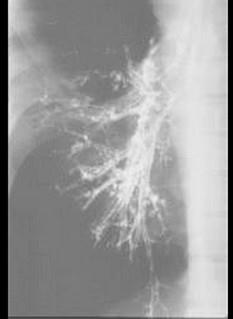

问题 支气管碘油造影检查结果如图所示,该患者最有可能的诊断是 ( )

选项 A、支气管扩张 B、肺癌 C、肺结核 D、慢性支气管炎 E、肺炎

答案 A